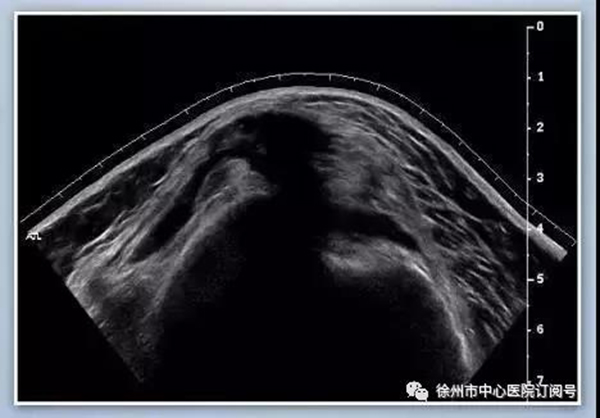

王阿姨為求進(jìn)一步診治,遂到徐州市中心醫(yī)院康復(fù)科就診,在經(jīng)過(guò)常規(guī)檢查,和病情討論后,決定為王阿姨實(shí)施肌骨超聲引導(dǎo),在肌骨超聲引導(dǎo)下抽出關(guān)節(jié)腔積液再藥物注射治療,治療后王阿姨疼痛明顯緩解。幾天后王阿姨好轉(zhuǎn)出院,很滿意治療效果。一周后復(fù)診,王阿姨說(shuō)這一周疼痛減輕了很多,睡眠也變很好,非常感謝徐州市中心醫(yī)院康復(fù)科的醫(yī)生和護(hù)士們!

肌骨超聲是指使用高頻超聲(5-13MHz)診斷人體軟組織、肌腱、神經(jīng)、骨骼和關(guān)節(jié)病變的一種超聲檢查方法。肌肉-骨骼系統(tǒng)超聲能夠提供更細(xì)微的軟組織分辨率,是能夠顯示肌腱和神經(jīng)等結(jié)構(gòu)的重要影像手段,在診斷關(guān)節(jié)、肌肉、肌腱、韌帶、筋膜、滑膜及周?chē)窠?jīng)疾病中有不可替代的作用。

肩部疼痛治療方法以往通常采用物理療法和藥物治療,當(dāng)疼痛明顯,肩關(guān)節(jié)粘連(凍結(jié)肩),一些常規(guī)方法不能很快緩解的情況下,選擇神經(jīng)阻滯和關(guān)節(jié)腔囊內(nèi)注射是有效的治療方法,超聲作為該治療方法下的輔助工具是一種非常靈活的臨床檢查,安全無(wú)輻射,顯著提高穿刺的成功率和療效,減少并發(fā)癥,在慢性疼痛治療中已被臨床醫(yī)生和患者廣泛接受。超聲引導(dǎo)下慢性肩周?chē)弁醋⑸涫墙橛诒J刂委熍c手術(shù)治療之間的微創(chuàng)介入治療手段,注射部位以診斷為依據(jù),包括肩關(guān)節(jié)、相關(guān)神經(jīng)阻滯和關(guān)節(jié)囊注射。常見(jiàn)的神經(jīng)阻滯部位為肩胛上神經(jīng),而關(guān)節(jié)囊注射部位通常為肩峰下,肩鎖關(guān)節(jié)或者關(guān)節(jié)腔內(nèi)注射。